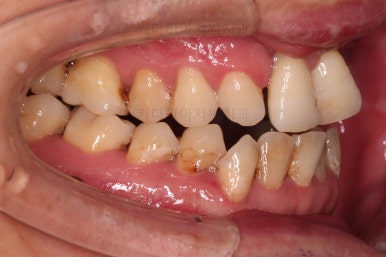

1. 초진 시 입안의 모습

부산구순구개열교정 키다리아저씨치과에 처음 내원하셨을 당시의 입안의 모습입니다.

이번 환자분도 이와 같은 일반적인 특징이 그대로 나타나 있었습니다.

양측성 구순구개열이었으므로 작은 앞니(대문니와 송곳니 사이)가 양쪽 다 결손이었고, 또 다른 이유로 아래 앞니도 1개 없는 상태였습니다.

초기 단계의 주안점은 아랫니와 악궁과 어울리는 윗니 악궁의 형태를 만들어 주는 것이고요.

악궁확장장치를 사용하지 않은만큼 철사의 형태를 잘 잡아가면서 악궁 형태를 개선시킵니다.

교정 10개월째인데, 악궁형태 많이 좋아졌고, 가지런한 느낌도 많이 좋아졌습니다.